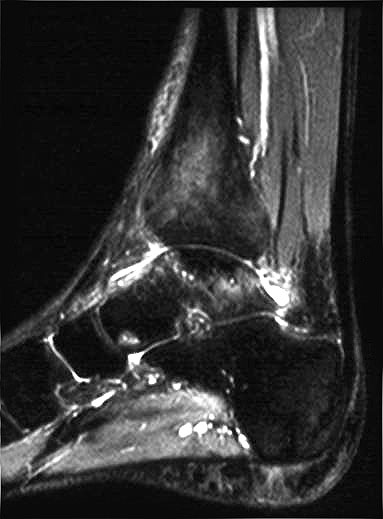

Mitunter kommt es im Krankheitsverlauf zur verzögerten Migration des Ödems in benachbarte Skelettabschnitte (z.B. Migration vom Talus in die distale Tibia oder in den Kalkaneus) (Abb. 2 und 3), was den Krankheitsverlauf erheblich prolongieren kann.

Beim TKMÖ ist in der Regel nach ca. 6-10 Monaten ab Einsetzen der ersten Symptome mit einer vollständigen Restitutio (Abb. 8 und 9) ist zu rechnen {ref: 21733459, 15045549, 15767100, 20640992, 18353586, 15049532}

Der Krankheitsverlauf verlängert sich  bei der Migration des Ödems um mehrere Monate 1617.